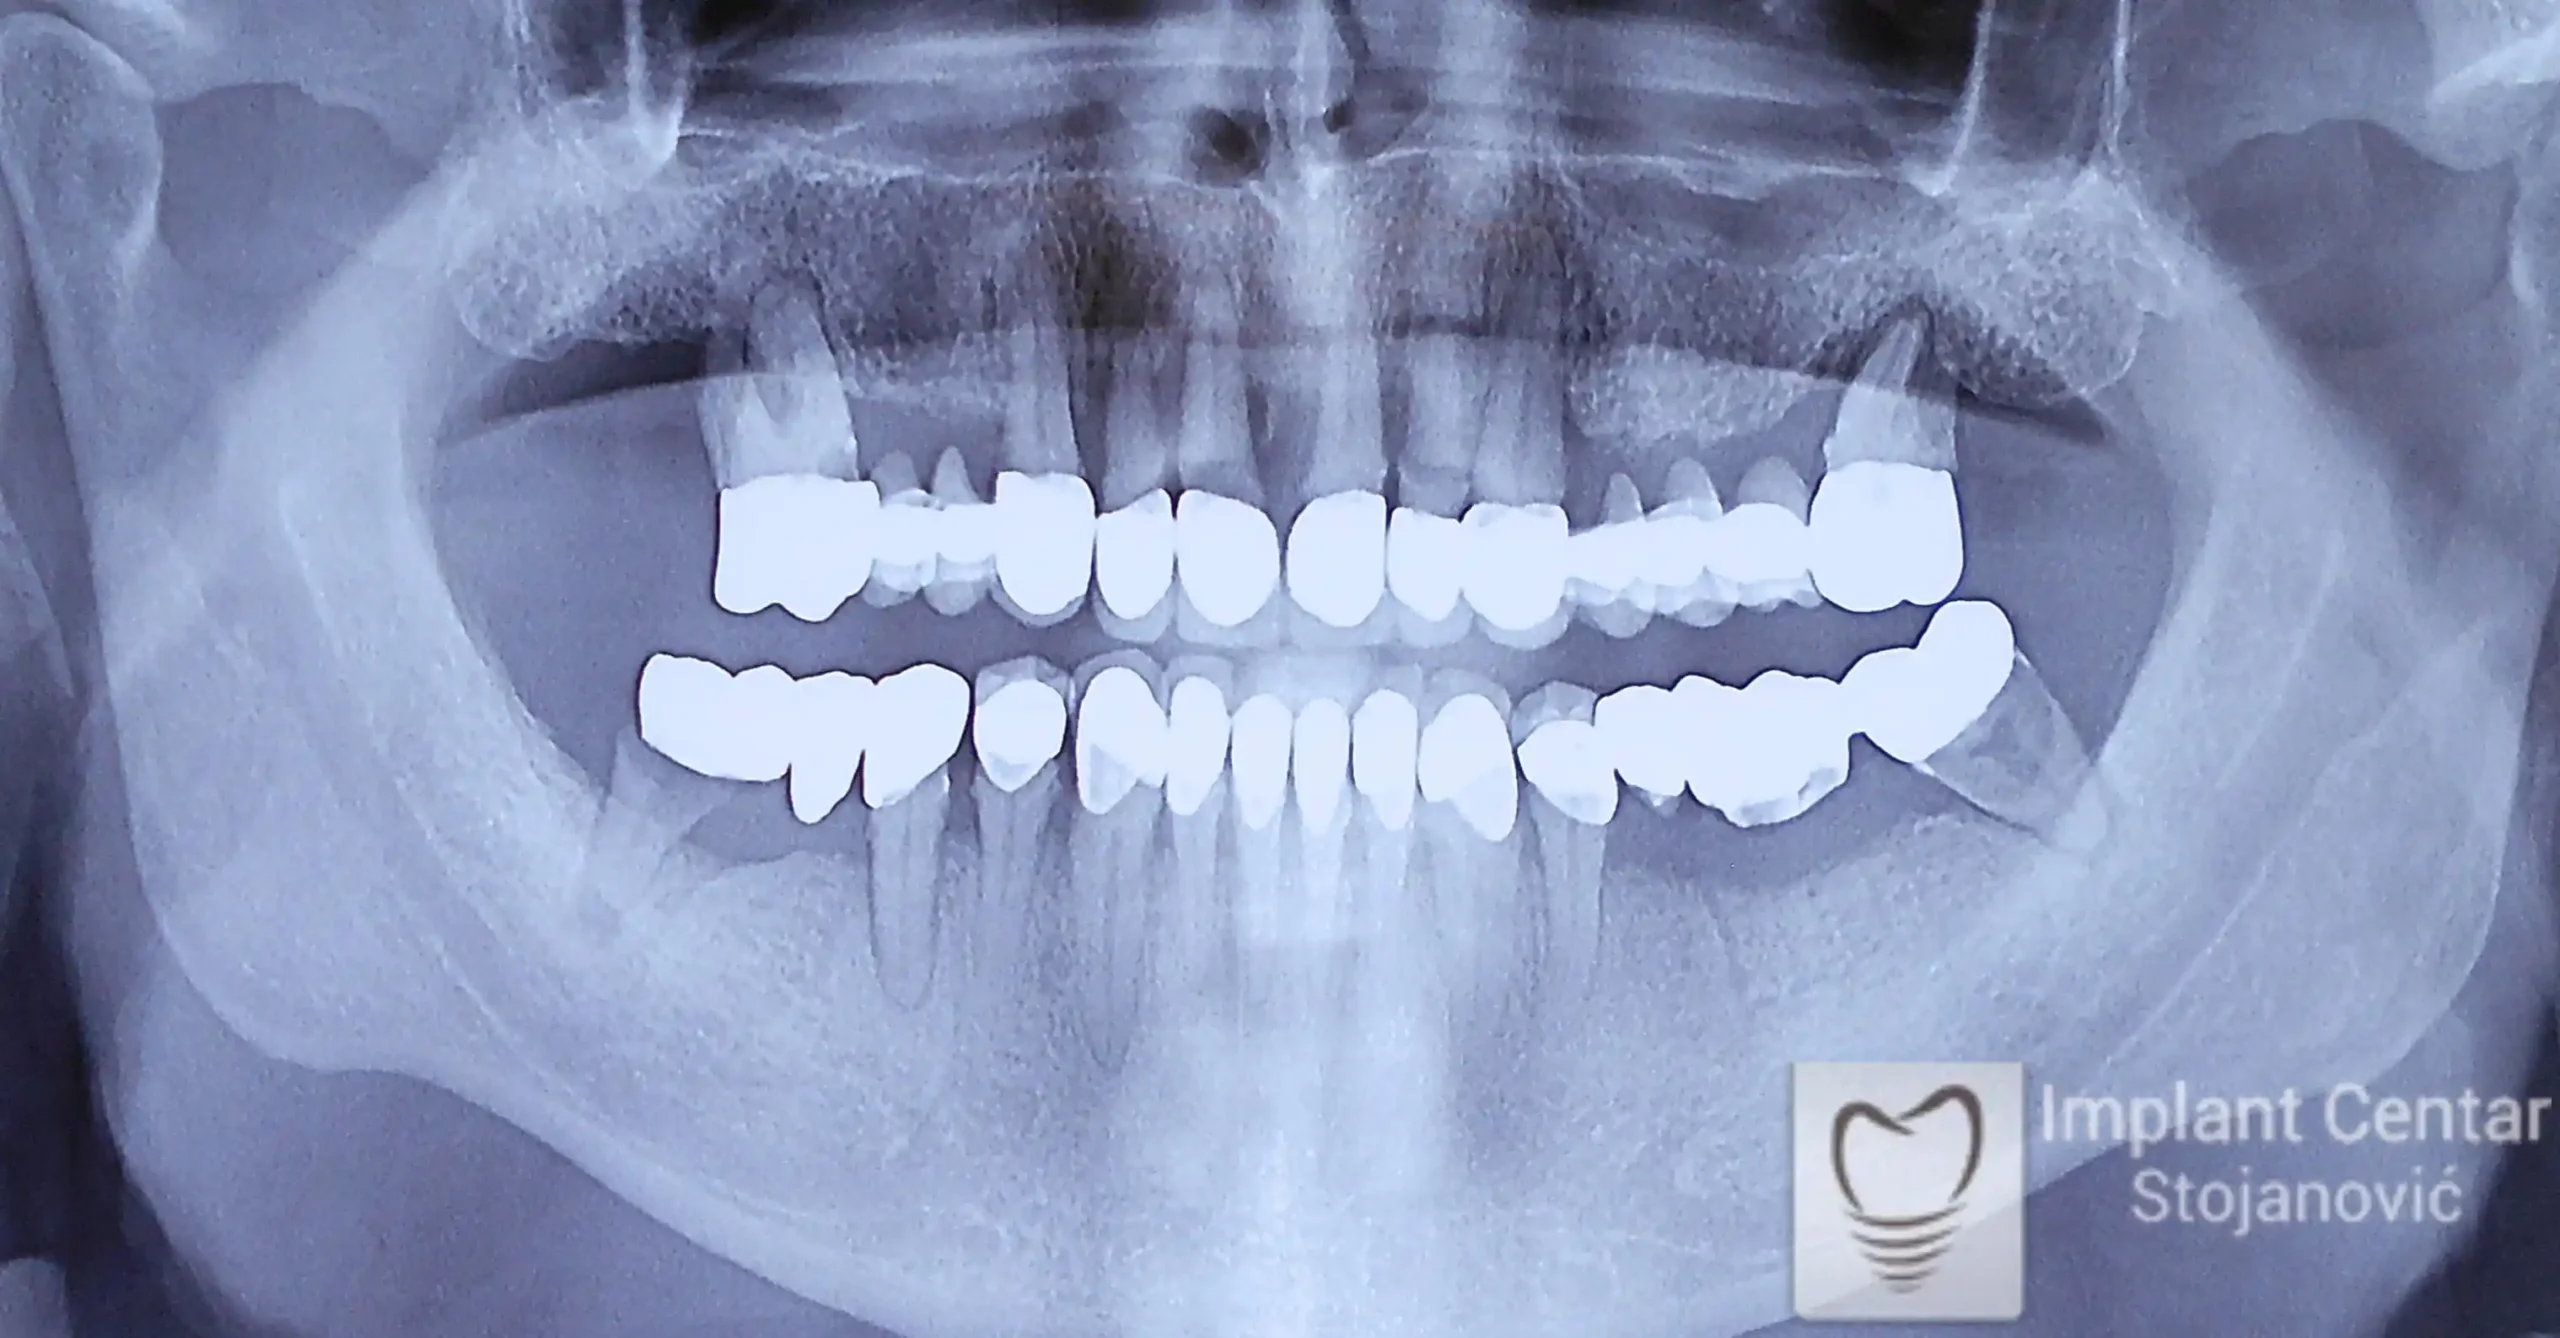

Na slici 1. i slici 2. prikazan je izgled pacijenta pre početka terapije – klinički i rendgenološki.

Nakon vađenja zuba, ugrađeni su implantati. Na slici 3 prikazan je ortopan snimak sa ugrđenim implantatima. Tokom perioda osteointegracije, pacijent je bio zbrinut fiksnim privremenim krunicama na implantatima, koje su izrađene samo dva dana nakon hirurške intervencije.